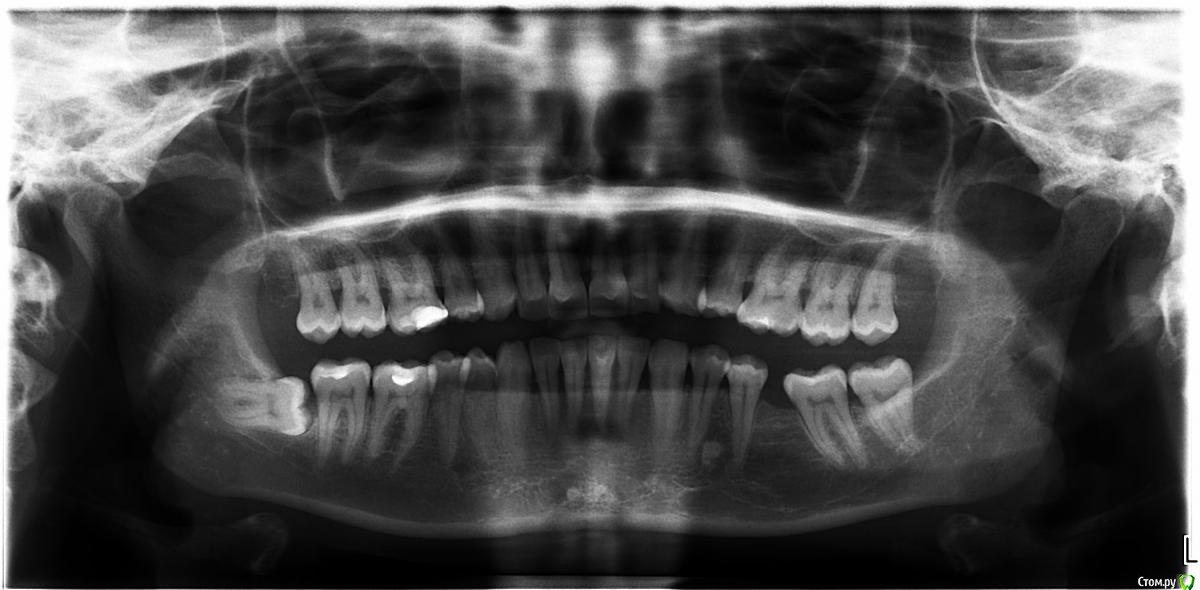

kurnosaya Опубликовано 13 августа, 2015 Поделиться Опубликовано 13 августа, 2015 Уважаемые доктора, доброго времени суток, у меня следующая проблема: рецессия десны в области нижних резцов, два месяца назад покраснела и начала гноится.Сделали депульпирование левой единички, положили лекарство. Была на приеме у многих врачей, советы расходятся. Кто-то предлагает вырвать всю группу нижних резцов, поставить два импланта и четыре коронки, кто-то предлагает депульпировать все остальные резцы, положить лекарство, пролечить таким образом десну, сделать открытый кюретаж впоследствии, затем гингивопластику. А также варианты: пластика уздечки и вестибулопластика, после чего также гингивопластика. Прикрепляю фотографии десны и ОПТГ. Прошу подсказать, какое лечение в моем случае будет самым верным? Ссылка на комментарий

faity Опубликовано 13 августа, 2015 Поделиться Опубликовано 13 августа, 2015 убираем восьмерки, ставим брекеты, ставим имплант, снимаем брекеты, ставим коронку, делаем тонельную пластику по необходимости, живём дальше простой спокойной жизнью до следующей проблемы.это по этапам 3 Ссылка на комментарий

zzkz Опубликовано 17 августа, 2015 Поделиться Опубликовано 17 августа, 2015 До брекетов рекомендовал бы закрыть рецессию. При необходимости после ортодонтии повторить. 1 Ссылка на комментарий